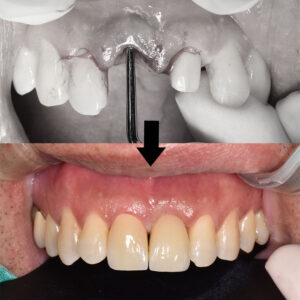

위 환자분은 30대의 여성분으로

과거 두개의 앞니가 연결된

브릿지를 사용하고 계셨는데요.

앞니로 사과를 베어먹다가

크라운이 빠져서 내원해 주셨어요.

왼쪽 앞니의 치아 내부에는 깊은

이차 우식이 발생하여 보존이 어려운 상태였고,

다행히 두 치아중 오른쪽 앞니는 치아 내부의 상태가

괜찮아 재 크라운 치료를 진행하고

한 치아만 발치 후 임플란트를 진행하기로 했어요.

환자분께서는 당장 내일 회사에 출근해야하는데

어떻게 해야하냐며 막막해 하셨는데요.

다행히 염증이 심해 발치를 한 케이스가 아니라

잔존 치조골 양이 양호하여 발치 즉시 임플란트 후

두 치아 모두 임시치아를 제작해 드리기로 하였어요.

발치 후 비어있는 공간에 임플란트를 식립하였고,

추후 잇몸이 꺼져 보이지 않도록

부족한 부분에는 뼈이식을 추가로 진행하였어요.

임플란트를 식립하고 지혈한 후,

임시치아까지 들어간 모습이에요.👏

옆에 재 크라운 치료를 진행할 치아도

함께 임시치아를 만들어 드렸는데요.

말 그대로 임시로 사용하는 치아지만

자연스럽게 제작되어 환자분께서도

만족하셨답니다😁

이제 이상태로 앞니 임플란트와

잇몸뼈가 단단히 유착되길 기다리게 되며,

약 3개월 후 최종 보철물을 제작했어요.

두 치아 모두 최종 보철물이 들어가고

치료가 마무리 되었어요.🦷